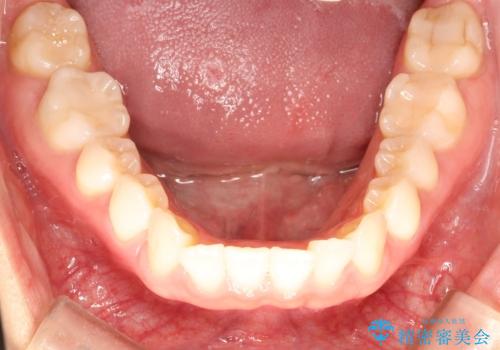

- 上の前歯のねじれを気にされて来院されました。

インビザラインを使用して矯正することとしました。